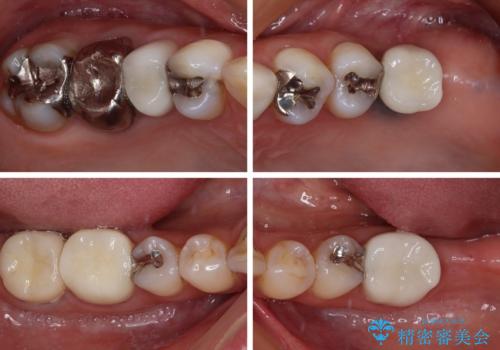

神経が除去されている歯、根管治療の必要な歯、むし歯の非常に大きな歯に対してオールセラミッククラウンにて補綴治療を行うこととしました。

左上の欠損部はインプラントを埋入した上で補綴することとしました。

途中通院されなかった時期が何度かあったため、初診から4年以上の年月がかかりましたが、比較的スムーズに治療を進めることができました。